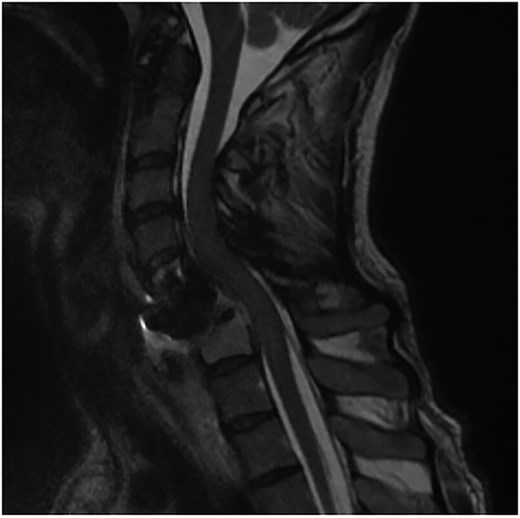

A 35-year-old male presented with a month-long history of dysphagia, severe headache, and posterior neck pain that radiated to the occiput. His medical history was significant for cervical surgeries, including an anterior cervical discectomy and fusion (ACDF) at C5/C6 one year and two months ago (Fig. 1). Shortly thereafter, the patient underwent revision surgery along with posterior plating from C5 to T1 due to osteomyelitis, worsening cervical deformity, and retropharyngeal abscess (Fig. 2). Initial workup included a noncontract computed tomography (CT), demonstrating increased gas density at C6 corpectomy site and post cricoid region (Fig. 3). A swallow study was obtained based on suspicion of a perforation and demonstrated extraluminal leakage of contrast posteriorly at the C6 level, consistent with initial CT (Fig. 4). Surgery included removal of the anterior and posterior hardware and esophageal repair. Although initially the esophageal injury was suspected to be related to the hardware, intraoperatively, it was found the instrumentation was not in communication with the esophagus. This confirmed the perforation was unrelated to direct injury from the cervical hardware construct, which was intact. The esophagus was repaired with a pectoralis flap. The postoperative course was uneventful, and the patient was discharged home after one week. The patient later died due to severe complications of substance abuse unrelated to the operation.

Initial sagittal CT without contrast after patient presented with symptoms of esophageal injury demonstrating increased gas density at the site of C6 corpectomy and post cricoid region.